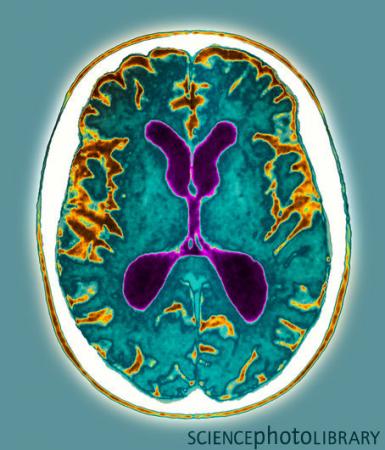

阿尔茨海默病患者的大脑图

“阿尔茨海默病”最早的记载可追溯到1906年,德国医生洛伊斯•阿尔茨海默在接诊51岁的女患者奥古斯特时,发现她5年前得了一种奇怪的病,记忆丧失,逐渐表现出语言障碍、糊涂、妄想且情绪激动。就诊时,她已经卧床不起,大小便失禁,而且还忘却了身边的人和事。奥古斯特死后,尸体解剖发现她的大脑由于神经元缺失而萎缩,脑中出现纤维缠结和斑块堵。

阿尔茨海默病是由神经病理学家阿尔茨海默于1906年首先发现,因此以他的名字命名。病征表现为此病能打乱大脑的正常工作,损害大脑中控制思维、记忆和言的部分,患者意识会越来越混乱,同时,情绪焦虑,记忆力衰退,渐渐无法自理生活。